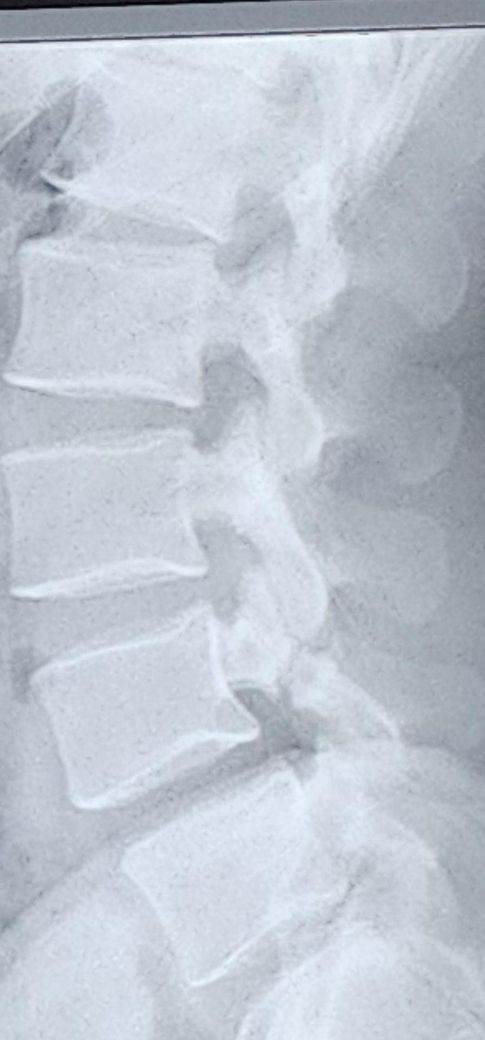

제 척추인데 저 주짓수나 운동 계속 해도 안전할지 봐주세요...

주짓수 두달만 더 하고 싶은데 너무 위험할까요..?

병 이름이 뭔가요?

저 주짓수나 헬스 계속 했다가 나중에 진짜 회복이

안될정도로 큰 후유증 남을 수 있나요?

후유증이나 큰 부상 걱정없이 주짓수 헬스 계속할 방법이 없을까요?척추분리증 호전되면 다시 후유증 생길 걱정없이 주짓수 할 수 있나요?

• 요추부 측면 엑스레이 사진 한 장을 놓고 구체적으로 어떻다 이야기를 할 수 없으며, 주짓수 등 운동을 더 하여도 될지 적합성에 대해선 판단을 내릴 근거가 되지 못합니다. 일단 사진만 놓고 본다면 크게 문제가 될만한 소견이 있어 보이는 엑스레이 사진으로 보이지는 않습니다.

허리의 만곡은 약간 후만이있지만 심하지는않고, 디스크의 공간도 찝히는 부분은 그리 보이지는 않지만 전체적인 사진이 아닌 일부분으로만 보여지기에 다소 차이가 있을 순 있습니다.